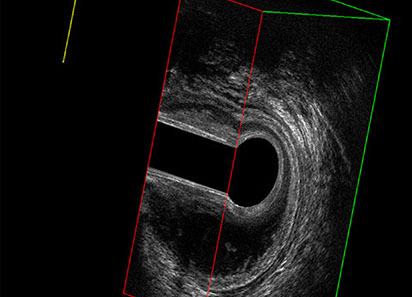

L’ecografia transanale è un esame diagnostico per immagini che consiste nell’introduzione di un trasduttore ad ultrasuoni. Le immagini qualitativamente migliori del canale anale sono ottenute usando un trasduttore rotante, montato in un manipolo rigido, che fornisce un’immagine a 360°. Con le apparecchiature più moderne è anche possibile ottenere immagini tridimensionali.

Proctal dispone di apparecchiatura per ecografia endoanale 3D con sonda rotante.